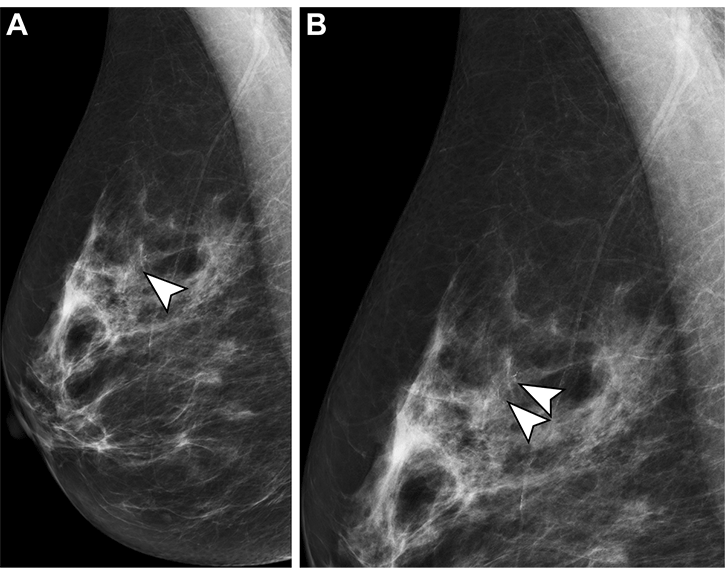

Маммограммы 54-летней женщины, проходящей второе скрининговое маммографическое обследование. (A) В верхней правой части молочной железы при медиолатеральной косой проекции имеются 15 мм плеоморфных микрокальцинатов (стрелка). (B) Микрокальцинаты (стрелки) лучше всего видны на этом увеличенном изображении. Рентгенолог, прочитавший маммограмму первым, не вспомнил об этом, а рентгенолог, прочитавший изображение вторым, вспомнил об этом. Биопсия под стереотаксическим контролем показала протоковую карциному высокой степени злокачественности in situ.